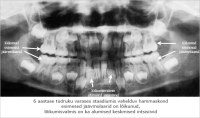

Eesmärk: Suu ja hammaste ülesannete kordamine, hammaste tähtsuse selgitamine ja näitlikustamine. Piima- ja jäävhammaste arvu, lõikumise nende tähtsuse ja vahetumise selgitamine.

Samuti õpitakse tundma hamba ehitust ning selgitatakse piima- ja jäävhammaste ning sülje tähtsust.